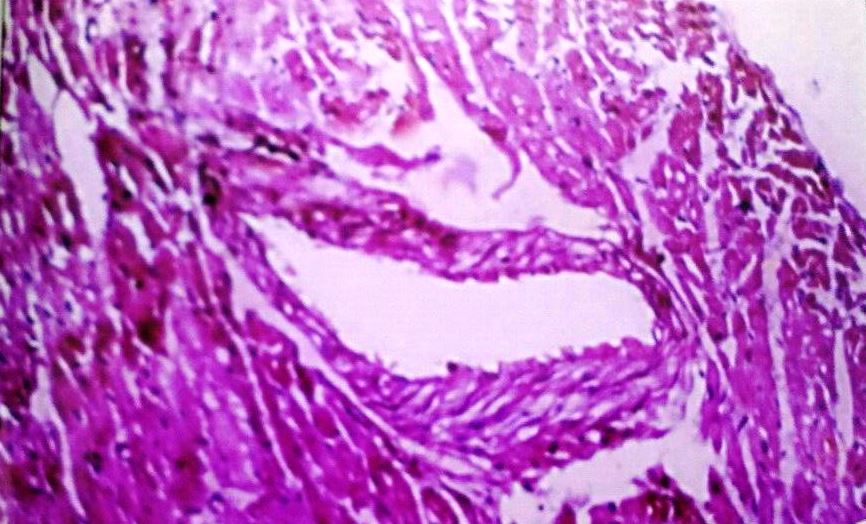

Coronary artery

The coronary artery of control group animals showed the lumen encircled by the arterial wall, which consisted of three distinct layers tunica intima, tunica media and tunica adventitia. The coronary arteries of hyper-cholesterolemic rabbits (Group II) showed foamy appearance, due to the presence of a large number of lipid-filled macrophages. The wall becomes very thick, reducing the size of the lumen. Our findings demonstrated that concurrent administration of C. verum extract with high cholesterol diet caused a significant increase in lumen size and thickening of tunica intima due to foam cell showed a reduction. However, the plaque has restricted to grow in concurrent groups, but coronary artery of low dose level treated group showed some fatty changes. (fig. 7-10)

Fig. 7: Coronary artery of control rabbit

Fig. 8: Coronary artery of rabbit after Athero Diet feeding for 120 d

Fig. 9: Coronary artery of rabbit–Athero Diet+C. verum 200 mg concurrent (120 d)

Fig. 10: Coronary artery of rabbit-Athero Diet+C. verum 300 mg concurrent (120 d)